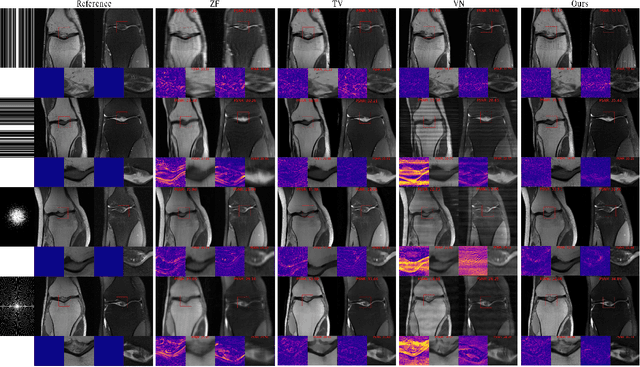

Abstract:Diffusion models have recently shown remarkable results in magnetic resonance imaging reconstruction. However, the employed networks typically are black-box estimators of the (smoothed) prior score with tens of millions of parameters, restricting interpretability and increasing reconstruction time. Furthermore, parallel imaging reconstruction algorithms either rely on off-line coil sensitivity estimation, which is prone to misalignment and restricting sampling trajectories, or perform per-coil reconstruction, making the computational cost proportional to the number of coils. To overcome this, we jointly reconstruct the image and the coil sensitivities using the lightweight, parameter-efficient, and interpretable product of Gaussian mixture diffusion model as an image prior and a classical smoothness priors on the coil sensitivities. The proposed method delivers promising results while allowing for fast inference and demonstrating robustness to contrast out-of-distribution data and sampling trajectories, comparable to classical variational penalties such as total variation. Finally, the probabilistic formulation allows the calculation of the posterior expectation and pixel-wise variance.

Abstract:Magnetic resonance imaging (MRI) is a potent diagnostic tool, but suffers from long examination times. To accelerate the process, modern MRI machines typically utilize multiple coils that acquire sub-sampled data in parallel. Data-driven reconstruction approaches, in particular diffusion models, recently achieved remarkable success in reconstructing these data, but typically rely on estimating the coil sensitivities in an off-line step. This suffers from potential movement and misalignment artifacts and limits the application to Cartesian sampling trajectories. To obviate the need for off-line sensitivity estimation, we propose to jointly estimate the sensitivity maps with the image. In particular, we utilize a diffusion model -- trained on magnitude images only -- to generate high-fidelity images while imposing spatial smoothness of the sensitivity maps in the reverse diffusion. The proposed approach demonstrates consistent qualitative and quantitative performance across different sub-sampling patterns. In addition, experiments indicate a good fit of the estimated coil sensitivities.